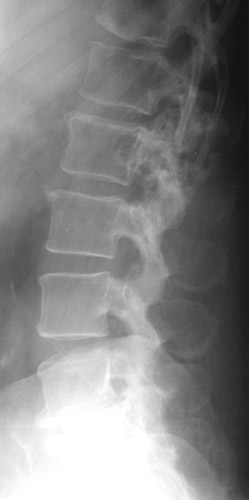

| The destructive lesion seen here on the left with a radiograph and on the right with T1 weighted MRI scan is a seen in the left pedicle of the L2 vertebra is a solitary plasmacytoma. The plasmacytoma is a mass of plasma cells that can produce a lytic lesion of bone. There can be deformity and pain. |